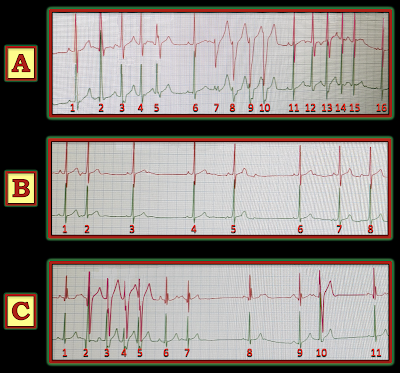

The 3 non-consecutive rhythm strips shown in Figure-1 — were obtained from a 24-hour Holter monitor, that was done on an athletic young teenage boy. The patient had a history of palpitations occurring both at rest and with activity. These 3 rhythm strips were representative of frequent arrhythmic activity that was seen during the course of 24-hour monitoring. An Echo on this patient was normal.

- How would YOU interpret these rhythm strips? Do the widened beats in A and C represent short runs of NSVT (Non-Sustained Ventricular Tachycardia)?

- PEARL #1: The 3 rhythm strips in Figure-1 show obvious variation with clear irregularity. Whenever I see a complex arrhythmia that contains different elements (some of which appear to be easier than others to interpret) — I always begin with the easier parts of the rhythm to interpret. Doing so often reveals the underlying rhythm — which then often facilitates interpreting the more difficult parts of the tracing.

The closest thing to an underlying sinus rhythm appears in Rhythm B. I suspect that the upper rhythm strip in each of the 3 tracings in Figure-1 (which is in RED) — is a standard lead II. If this is the case — then we are seeing normal-looking and upright P waves with a normal PR interval in front of beats #1, 4 and 5 — which means that the underlying rhythm is sinus (RED arrows in Rhythm B — as shown in Figure-2).

- Still looking at Rhythm B — The shape of the P waves in front of beats #3, 6, 7 and 8 looks slightly different than the shape of the P waves in front of beats #1,4,5 (PINK arrows highlighting slightly smaller P waves). The challenge is trying to determine if some (or all) of these PINK-arrow P waves represent sinus P waves (with some of the normal variation in sinus P wave morphology that is commonly seen due to artifact, movement, or random variation) — vs — P waves arising from another atrial focus.

- Looking next at Rhythm C in Figure-2: The difference in P wave size and shape between the RED-arrow P wave (before beat #9 in C) — vs the PINK-arrow P waves (before beats #1,8,11) — looks to be real! So at this point — I was thinking that the underlying rhythm in today’s tracing was sinus — and that there was ectopic atrial activity.

- Rhythm A in Figure-2 further supports this impression — with greatest difference in P wave size between the PINK-arrow P wave (before beat #16) — and the RED-arrow P waves (before beats #1,6,11 — which look to be larger in both monitoring leads of Rhythm A).